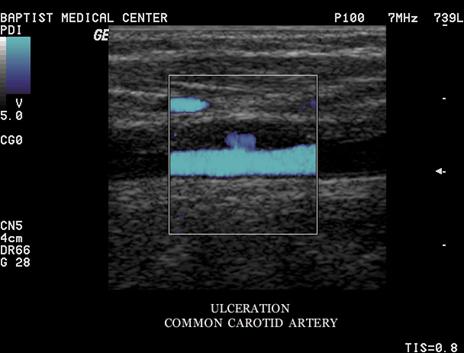

Ulcerative Plaque

A scooped out appearance

shelf like projections